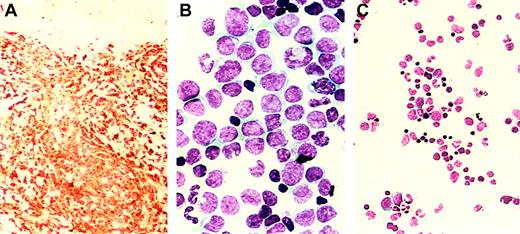

Six weeks after the initiation of EPO therapy, numerous violaceous nodules, each measuring 0.5 to 1 cm, appeared across the patient's back and abdomen. Biopsy specimens showed dermal infiltration by monoblasts staining immunohistochemically for lysozyme (Figure1A), myeloperoxidase, and CD15. Hemoglobin level was 9 g/dL, WBC count was 26.8 × 109/L with 41% neutrophils, 32% lymphocytes, 25% monocytes, 2% basophils, and 0% blasts, and platelet count was 203 × 109/L. The BM was hypercellular, with 45% monoblasts (Figure 1B) staining with α-naphthyl butyrate esterase and expressing CD45, HLADr, CD2, CD4, CD11b, CD11c, CD13, CD14, CD15, and CD33 by MFC with persistence of the B-cell clone. Karyotype was again normal, and MLL gene rearrangement was not detected in 500 interphase cells by fluorescence in situ hybridization with the LSI MLL dual-color rearrangement probe (catalog number 32-190083; Vysis, Downer's Grove, IL). A diagnosis of acute monoblastic leukemia (French-American-British type M5a AML) with leukemia cutis was made, but chemotherapy was not initiated because of comorbid conditions. EPO therapy was discontinued. Skin lesions regressed and disappeared completely by 7 weeks. A BM sample 3 weeks after the discontinuation of EPO showed reversion to MDS, without increased blasts (Figure 1C) and without abnormal myeloid cells by MFC; the B-cell clone persisted. Anemia worsened again, necessitating transfusions. The patient had a fatal myocardial infarction 4 months later; leukemia had not recurred.

Erythropoietin-dependent acute monoblastic leukemia.

Histopathology. Skin biopsy showing infiltration by monoblasts staining with lysozyme (panel A, × 50 magnification) and bone marrow aspirate smear showing acute monoblastic leukemia (panel B, × 200 magnification), both during EPO therapy. Bone marrow aspirate smear showing the absence of leukemia 3 weeks after the discontinuation of EPO therapy (panel C, × 50 magnification).